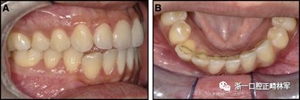

臨床檢查顯示固定保持器完好,弓絲沒有斷裂(圖13)。在下頜右側(cè)中切牙唇側(cè)和鄰近側(cè)切牙的舌側(cè)注意到有牙齦退縮。這些牙齒在退縮方向上存在顯著的扭矩差異。下頜的左側(cè)尖牙頰側(cè)錯(cuò)位,而右側(cè)尖牙舌側(cè)傾斜。三維射線照片證實(shí)了下頜右側(cè)尖牙面?zhèn)妊啦酃菃适?,右?cè)中切牙的喪失程度較輕。右側(cè)側(cè)切牙根也從舌側(cè)骨面上扭轉(zhuǎn)出來(圖14)。

圖13.粘合到尖牙和切牙上的柔性螺旋弓絲保持器,伴有牙齦退縮和附著喪失,中切牙之間嚴(yán)重的扭矩差異以及兩顆尖牙的橫向移動和扭矩。牙周問題和牙齒移動的嚴(yán)重程度均為牙周正畸聯(lián)合治療的指征:A,正面視圖; B,咬合面視圖。